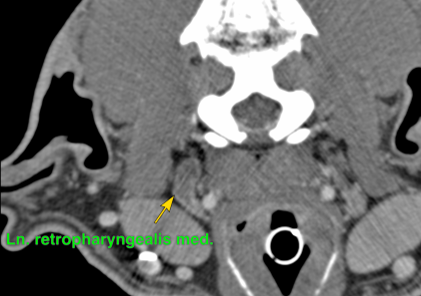

Bei Rottweiler Rocky war die Nickhaut bereits seit Wochen etwas vorgefallen und im Ultraschall erhärtet sich der Verdacht auf einen Tumor. Im CT konnte dann eine riesige Masse dargestellt werden und auch ein vergrößerter Lymphknoten. Die Biopsie ergab einen Tumor unklarer Herkunft, sodass wie zuerst keine sichere Prognose stellen konnten. Aber es sah nicht gut aus.